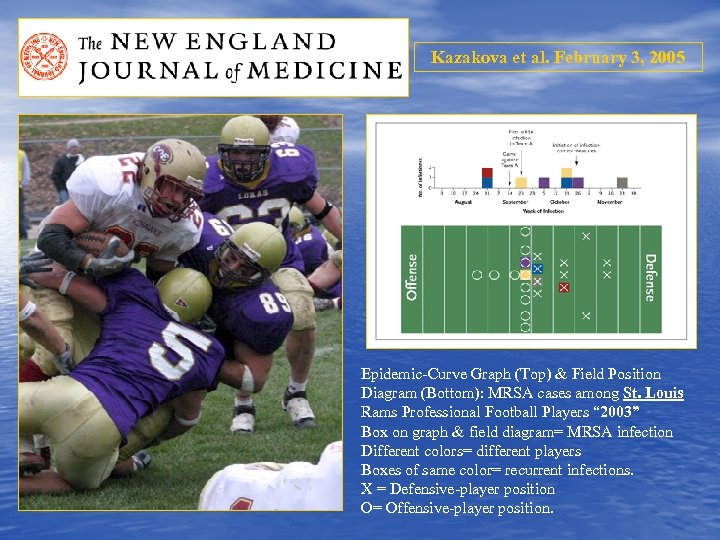

Kazakova et al. February 3, 2005 Epidemic-Curve Graph (Top) & Field Position Diagram (Bottom): MRSA cases among St. Louis Rams Professional Football Players “ 2003” Box on graph & field diagram= MRSA infection Different colors= different players Boxes of same color= recurrent infections. X = Defensive-player position O= Offensive-player position.

Kazakova et al. February 3, 2005 Epidemic-Curve Graph (Top) & Field Position Diagram (Bottom): MRSA cases among St. Louis Rams Professional Football Players “ 2003” Box on graph & field diagram= MRSA infection Different colors= different players Boxes of same color= recurrent infections. X = Defensive-player position O= Offensive-player position.

Kazakova et al. February 3, 2005 • • • Retrospective cohort study Nasal Swab Survey 84 St. Louis Rams football players & staff members. S. aureus analyzed by PFGE & Gene typing During the 2003 football season: ● 8 MRSA infections: 5/58 Rams players (9 %) ●All infections developed at turf-abrasion sites ●Infection was significantly associated with the lineman or linebacker position & higher BMI. ●MRSA : whirlpools and taping gel ●MRSA : 35/ 84 nasal swabs from players and staff members (42%). ●MRSA : competing football team had PFGE patterns that were indistinguishable from those of the Rams' ●MRSA: All positive PVL & SCC mec type IVa resistance

Kazakova et al. February 3, 2005 • • • Retrospective cohort study Nasal Swab Survey 84 St. Louis Rams football players & staff members. S. aureus analyzed by PFGE & Gene typing During the 2003 football season: ● 8 MRSA infections: 5/58 Rams players (9 %) ●All infections developed at turf-abrasion sites ●Infection was significantly associated with the lineman or linebacker position & higher BMI. ●MRSA : whirlpools and taping gel ●MRSA : 35/ 84 nasal swabs from players and staff members (42%). ●MRSA : competing football team had PFGE patterns that were indistinguishable from those of the Rams' ●MRSA: All positive PVL & SCC mec type IVa resistance